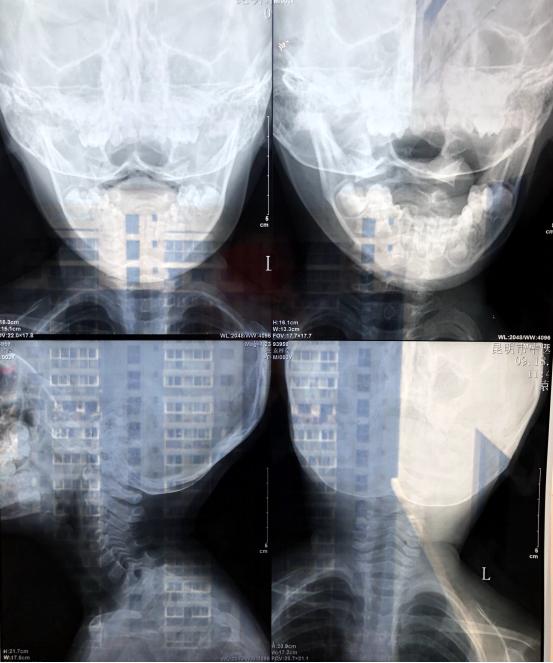

患者今年三岁,有外伤史(从床上摔下来)现在低头的时候头会疼。

李维新 教授:从患者的CT来看,没有明显的骨性结构异常,应该没有大碍。

李维新 教授:从现在的情况来看,没有什么明显的异常,也没有治疗的必要,但是需要加强观察,出现异常以后及时到医院就诊。